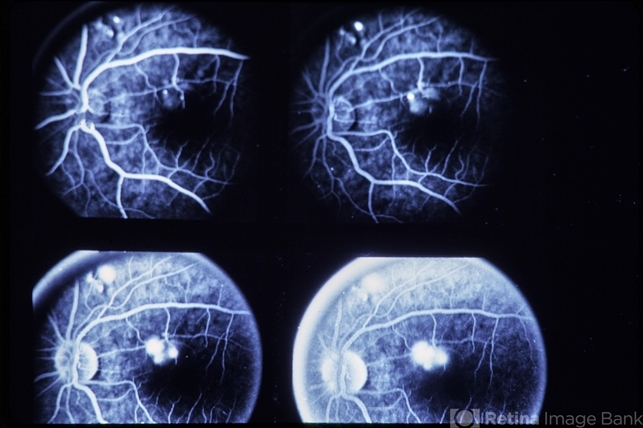

Central Serous Retinopathy

central serous retinopathy (CSR)

Central serous retinopathy.